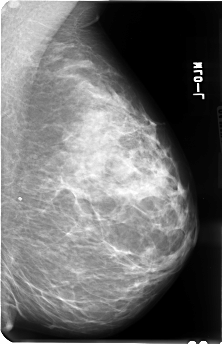

B_3040_1.RIGHT_MLO

FILE: B_3040_1.RIGHT_MLO.OVERLAY

TOTAL_ABNORMALITIES 2

ABNORMALITY 1

LESION_TYPE MASS SHAPE IRREGULAR MARGINS SPICULATED

ASSESSMENT 4

SUBTLETY 4

PATHOLOGY MALIGNANT

ABNORMALITY 2

LESION_TYPE MASS SHAPE OVAL MARGINS CIRCUMSCRIBED

ASSESSMENT 3

SUBTLETY 3

PATHOLOGY UNPROVEN